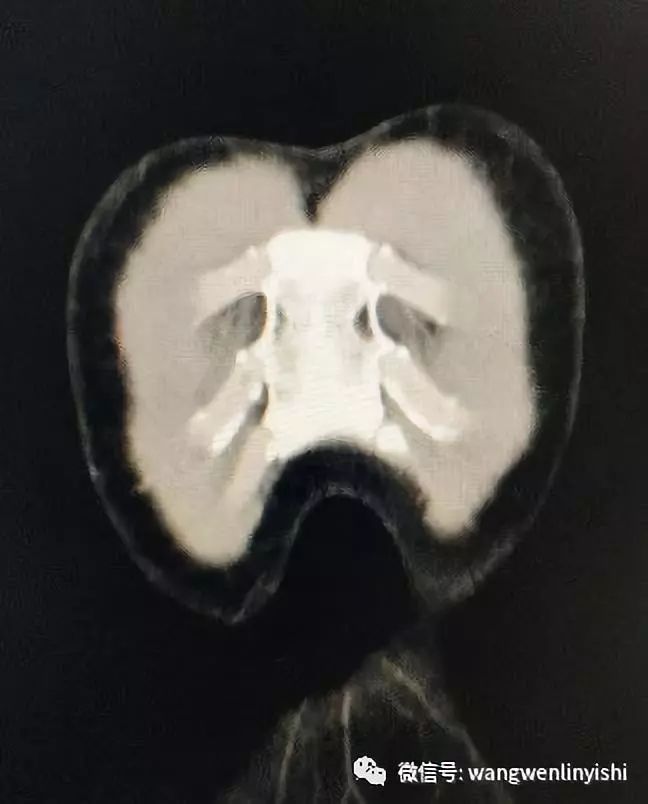

入院查体,前胸壁明显畸形,上半胸壁前突,以正中最明显,突起向下延伸,两侧胸壁下缘呈弧形下垂,正中凹陷。凹陷底部可见心脏搏动。双肺呼吸音清晰,未闻及啰音。心率较快,90次/分,未闻及杂音。X线检查提示前胸壁上半突起,下半局部凹陷。CT提示前胸壁前突。

(前胸壁明显畸形。)

(前胸壁呈典型Wenlin胸改变。)

(前胸壁下方凹陷。)

(前胸壁上部明显前突。)